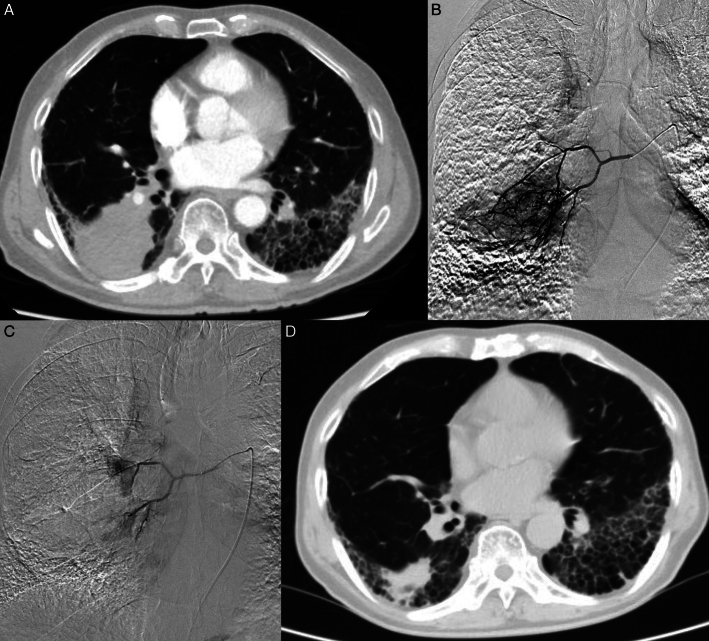

Background: Bronchial arterial chemoembolization (BACE), as a safe and effective minimally invasive treatment method, is increasingly being accepted by more and more patients with advanced nonsmall-cell lung cancer (NSCLC). In recent years, drug-eluting beads (DEB)-BACE has also been applied in the field of lung cancer. It is still unclear which is more recommended due to the limited number of comparative studies between conventional BACE (C-BACE) and DEB-BACE.

Purpose: To compare the safety and efficacy of C-BACE (BACE with gelfoam particles) and DEB-BACE for advanced NSCLC.

Materials and methods: From January 2021 to April 2023, 48 consecutive patients (37 males and 11 females) with advanced NSCLC treated with DEB-BACE (group A) or C-BACE (group B) at our center were collected retrospectively in this study. There were 18 patients in group A and 30 patients in group B. The technical success rate, adverse events, objective response rate (ORR), disease control rate (DCR), progression-free survival (PFS), and overall survival (OS) were compared between the 2 groups.

Results: The technical success rate in both groups was 100%. The median OS times were 19.5 months and 12.5 months in group A and group B, respectively ( P =0.0062). The median PFS times were 13 months and 7 months in group A and group B, respectively ( P =0.0072). The ORRs at 6 months were 72.2% and 46.7% in group A and group B, respectively ( P =0.084). The DCRs at 6 months were 88.9% and 63.3% in group A and group B, respectively ( P =0.043). Grade 1 adverse events like chest pain, and cough were common, while serious adverse events did not occur.

Conclusions: BACE with DEB or gelfoam particles were equally safe. The DEB-BACE showed better survival and tumor response than C-BACE for advanced NSCLC.